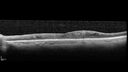

NPDR and Severe macular ischemia sudden vision loss

60 year old female with sudden vision loss OD 1 week ago. VA 20/63, 20/200. OCT-A and FA shows severe macular ischemia OU